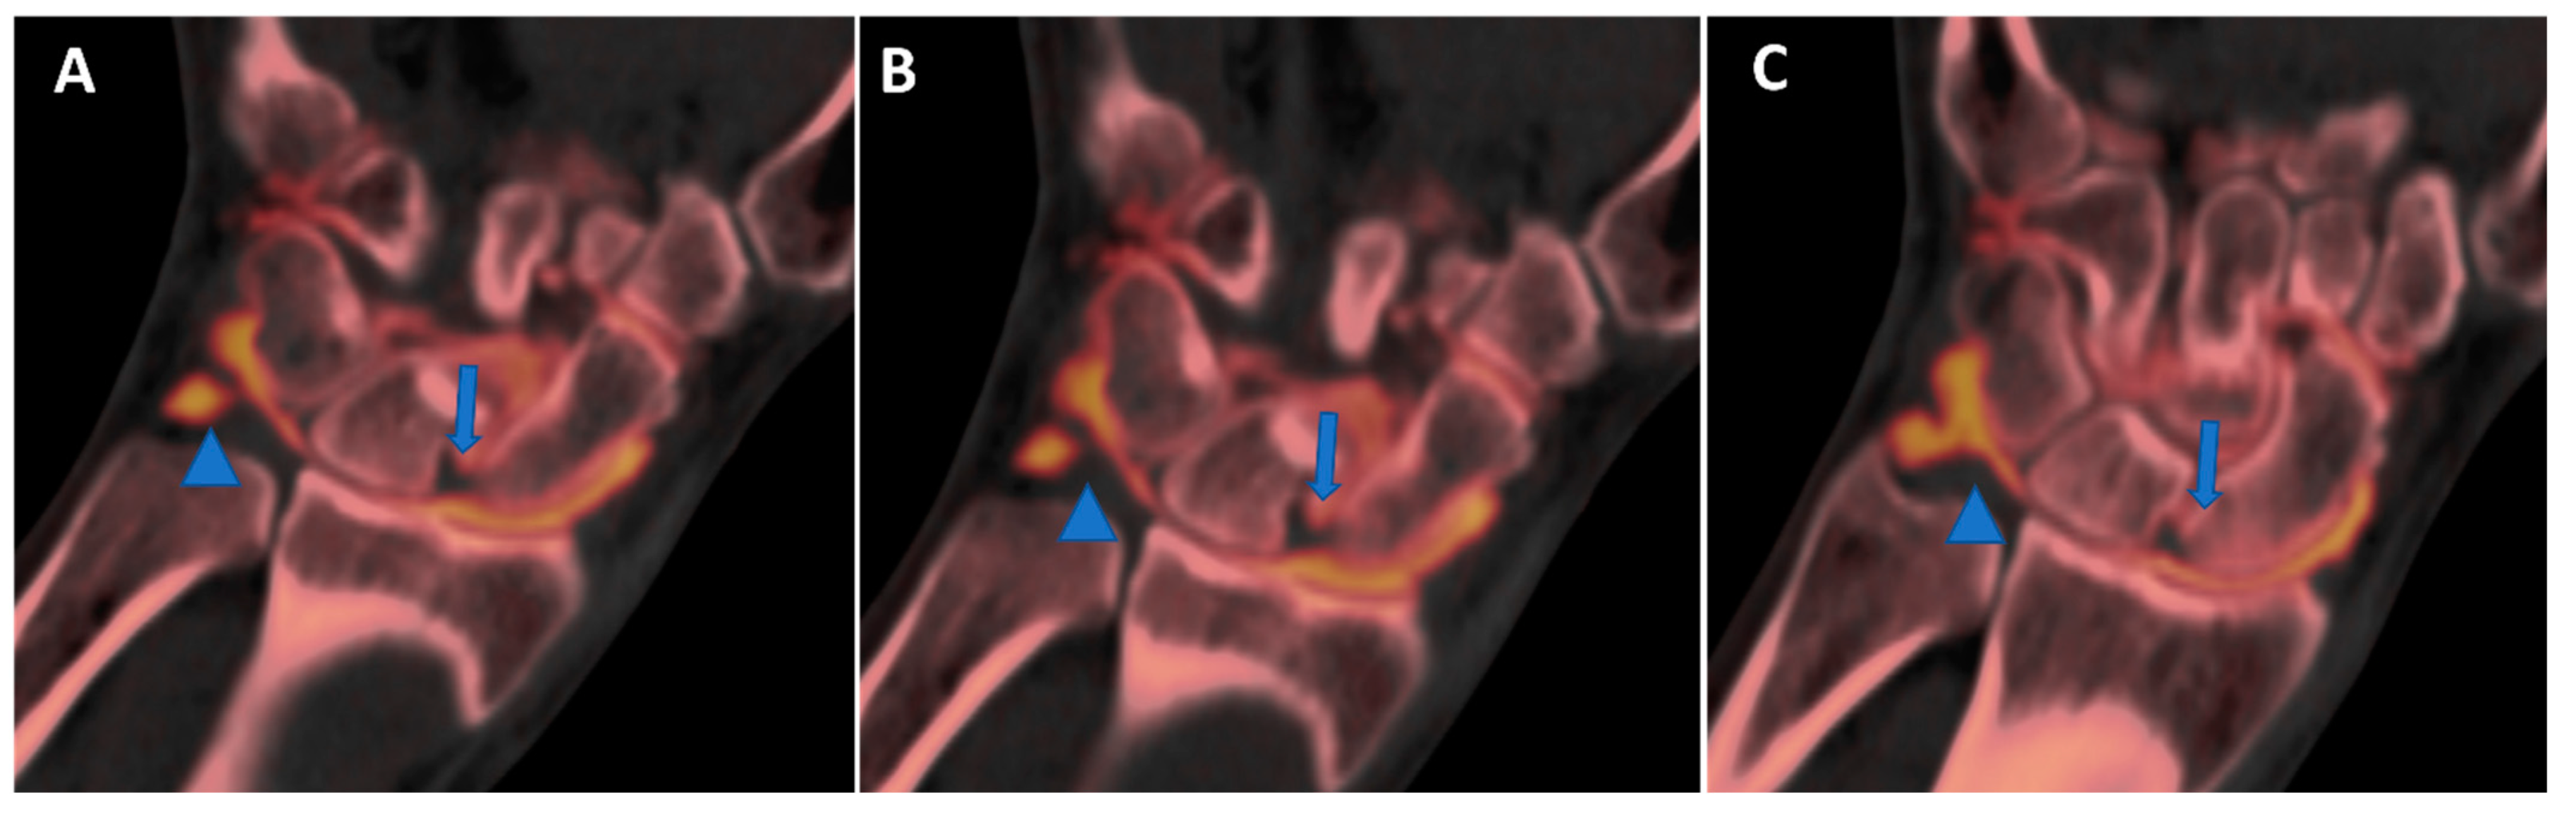

Figure 10. High-spatial-resolution wrist anatomy using DECTA. On the 0.4 mm coronal DECTA iodine map images (AC), a triangular fibrocartilage complex (arrowhead) and a scapho-lunate ligament (arrow) are nicely depicted.

One of the major intrinsic advantages of CT is the possibility of achieving high spatial resolution images with bone or soft-tissue windows [39]. In clinical practice, recent DECT scanners allow for 0.3 mm isotropic images that can be reconstructed on any imaging plane, simulating rotational images acquired on MRI and correctly evaluating complex anatomic structures. Additionally, thanks to the additional advantage of the intrinsic high contrast resolution of DECT, these images can help with the visualization of cartilages, intra-articular plicae, and the normal anatomy of tiny anatomic structures in small joints of the wrist (Figure 8, Figure 9 and Figure 10).